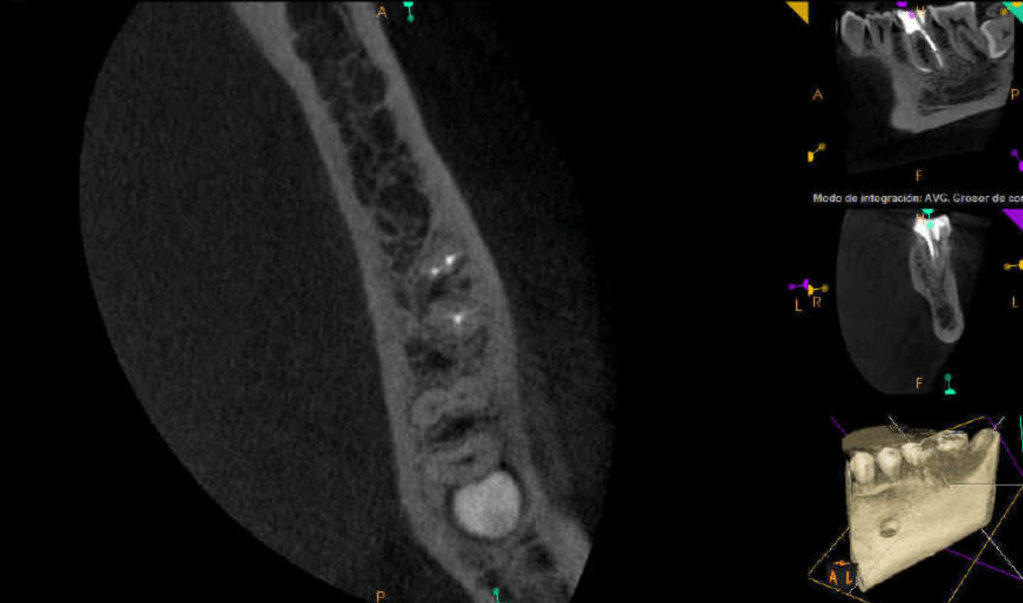

Molar inferior, conducto CM

Molar inferior, conducto MC, Reeco prendo